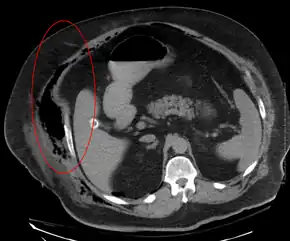

Medical imaging

Imaging has a limited role in the diagnosis of necrotizing fasciitis. The time delay in performing imaging is a major concern. Plain radiography may show subcutaneous emphysema (gas in the subcutaneous tissue), which is strongly suggestive of necrotizing changes, but it is not sensitive enough to detect all the cases, because necrotizing skin infections caused by bacteria other than clostridial infections usually do not show subcutaneous emphysema. If the diagnosis is still in doubt, computed tomography (CT) scans and magnetic resonance imaging (MRI) are more sensitive modalities than plain radiography. However, both the CT scan and MRI are not sensitive enough to rule out necrotizing changes completely.[2] CT scan may show fascial thickening, edema, subcutaneous gas, and abscess formation.[2] In MRI, when fluid collection with deep fascia involvement occurs, thickening or enhancement with contrast injection, necrotizing fasciitis should be strongly suspected. Meanwhile, ultrasonography can show superficial abscess formation, but is not sensitive enough to diagnose necrotizing fasciitis.[2] CT scan is able to detect about 80% of cases, while MRI may pick up slightly more.[18]